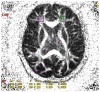

Schizophrenia is characterized by complex metabolic dysregulations and their consequences. Until now, numerous theories have explained its pathogenesis, using a spectrum of available technologies. We focused our interest on lipid profile-periphery high-density cholesterol level and lipoproteins in the human brain and compared magnetic resonance imaging (MRI) scans of patients with schizophrenia and the healthy group. Detailed analysis of biochemical parameters was performed using magnetic resonance spectroscopy. Our study aimed to reveal correlations between periphery high-density lipoproteins levels and lipoproteins in the brain, depicted in MRI scans, and parameters of peripheral oxidative stress expressed as paraoxonase. Patients with schizophrenia have decreased levels of high-density lipoproteins, low paraoxonase activity, and slightly raised sodium in the blood. Positive significant correlations between serum high-density cholesterol and anterior cingulate cortex, unique brain area for schizophrenia pathophysiology, MR spectroscopy signals, and diffusion have been revealed. To our knowledge, this is the first study to describe the effect of an anterior cingulate disorder on high-density cholesterol levels on the development of schizophrenia.